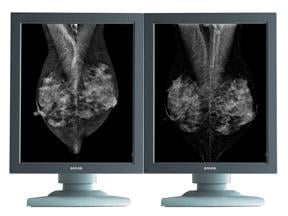

The Coronis 5 MP Mammo display system for digital mammography offers the latest display technology for high-bright diagnostics along with a series of DICOM-compliant displays for clinical review.

The system offers radiologists highly accurate grayscale images with high resolution, high contrast and perfect geometry. Innovative technology, such as per pixel uniformity, ensures pixel-perfect images, without disturbing screen-noise, which might hide subtle details.